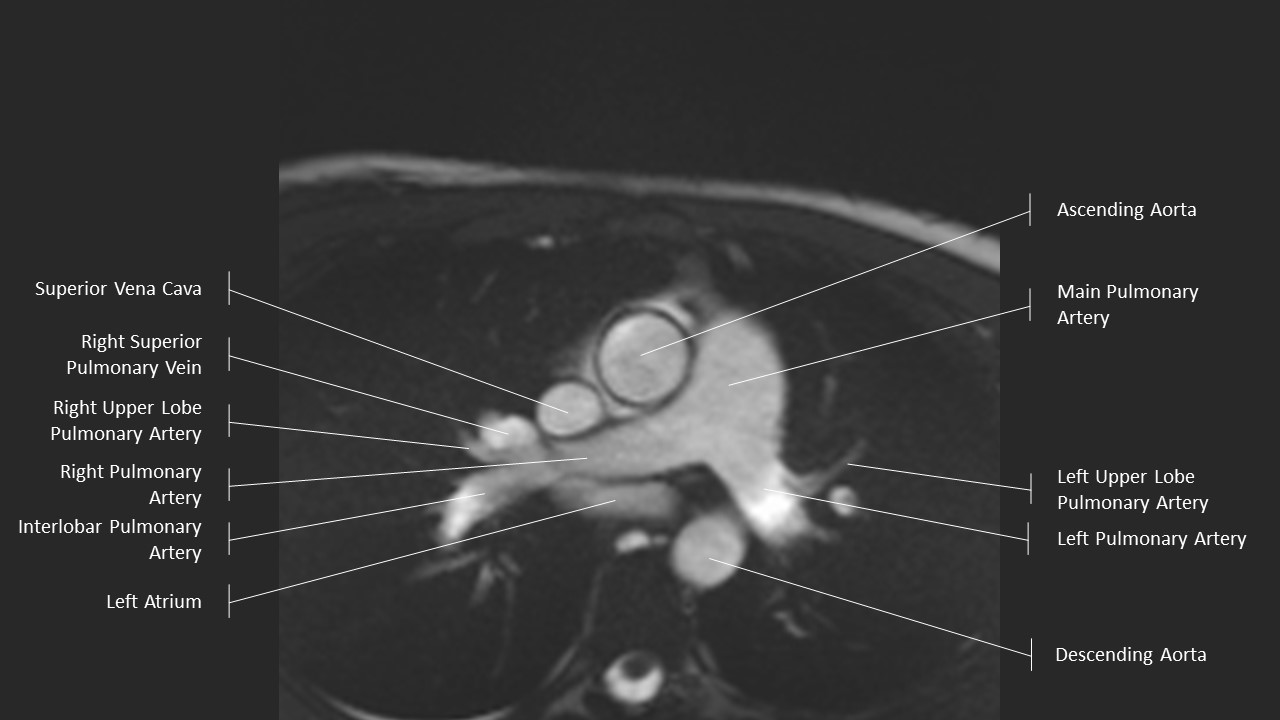

Axial Series